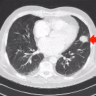

This case report describes the surgical treatment of a hydatid cyst in a 35-year-old patient.